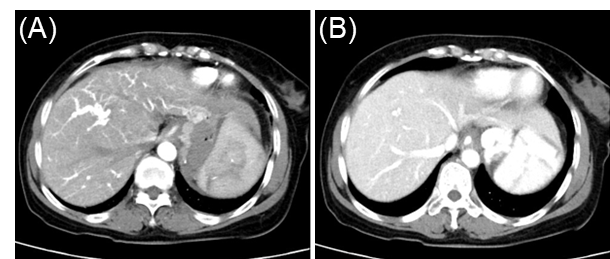

汤善宏教授:平原进入高原致血栓形成相关布-加综合征及门脉血栓复杂门脉高压病例分享

病史摘要:30岁男性,因“上腹不适6月,腹胀20天”入院。6月前无诱因出现上腹部不适、进食后腹胀,外院胃镜示反流性食管炎,肝功异常,对症治疗缓解。20天前出现全腹胀、黄疸、食欲降低、双下肢水肿。既往青霉素过敏,有吸烟、饮酒史,曾长期在高原工作。 诊疗过程:入院查体生命体征平稳,全身皮肤巩膜黄染,腹部膨隆,移动性浊音阳性。辅助检查提示布加综合征、肝硬化等。诊断为慢加急性